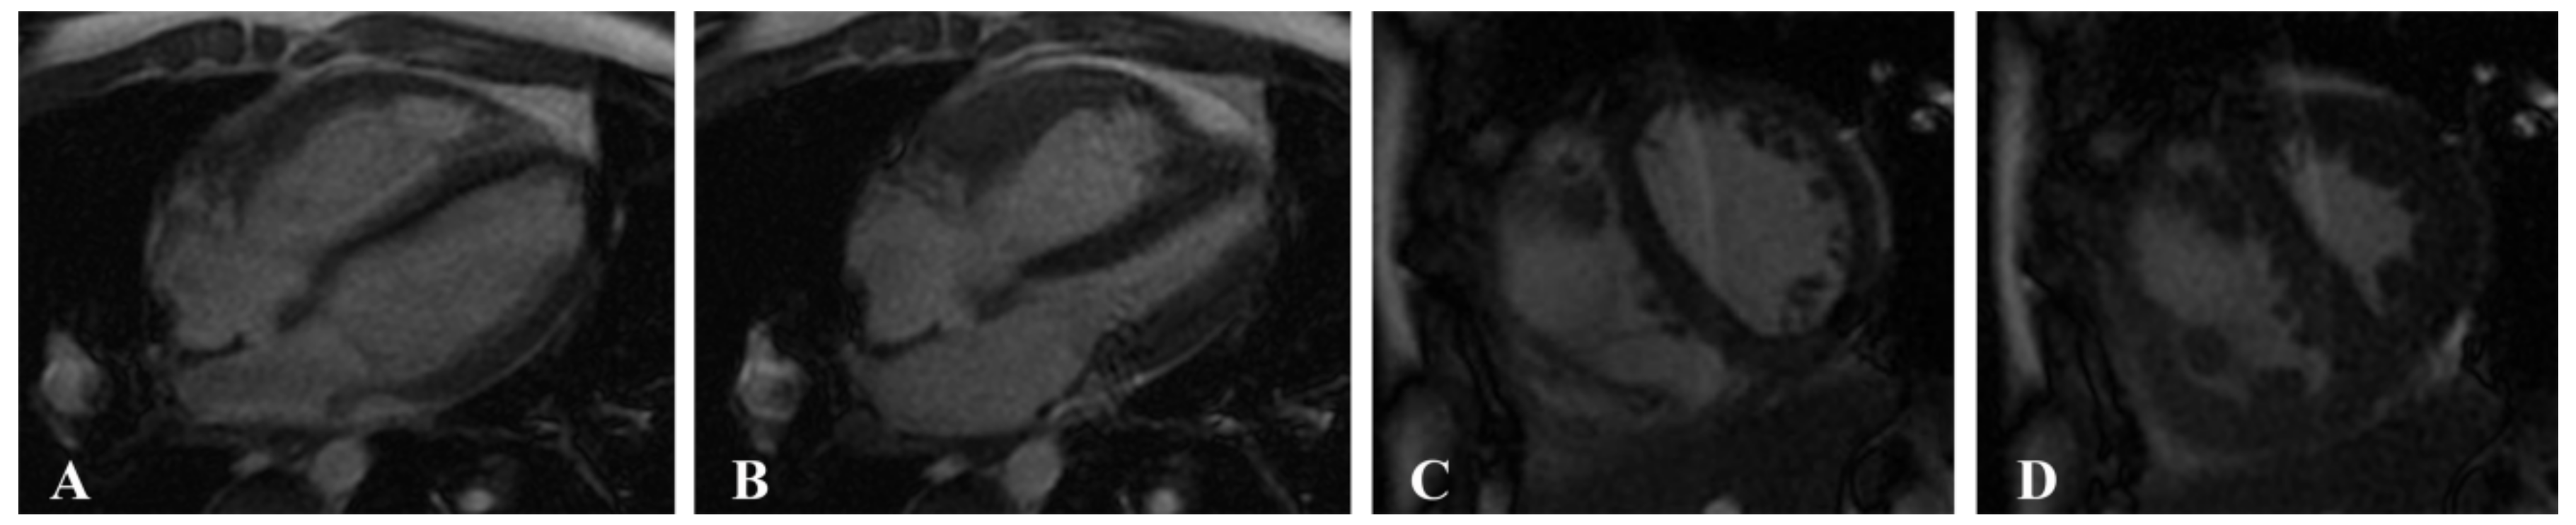

CMRI was performed using a 1.5-T system (Signa EXCITE HDx; GE Health care, Milwaukee, MI, USA) and a 3.0-T MR system (MAGNETOM Verio, Siemens Health care, Erlangen, Germany) with a 32-channel phased-array surface coil and MR-compatible ECG and respiratory gating. Multiphase cine imaging was performed using a standard steady-state free precession (SSFP) pulse sequence in the LV two-chamber and four-chamber long-axis views and in the biventricular short-axis views with breath holding (field of view (FOV) = 340 × 360 mm2, matrix = 256 × 192, TR = 51.45 ms, TE = 1.51 ms; short-axis planes: 10 or 8 mm thickness, 0 mm gap, matrix = 216 × 256) (Figure 1).

Figure 1.

Multiphase cine imaging was performed using a standard steady-state free precession (SSFP) pulse sequence in a 14-year-old male patient with pulmonary arterial hypertension (PAH). Four-chamber long-axis view at the end of diastole (A) and end of systole (B) and biventricular short-axis views at the end of the diastole (C) and the end of the systole (D).